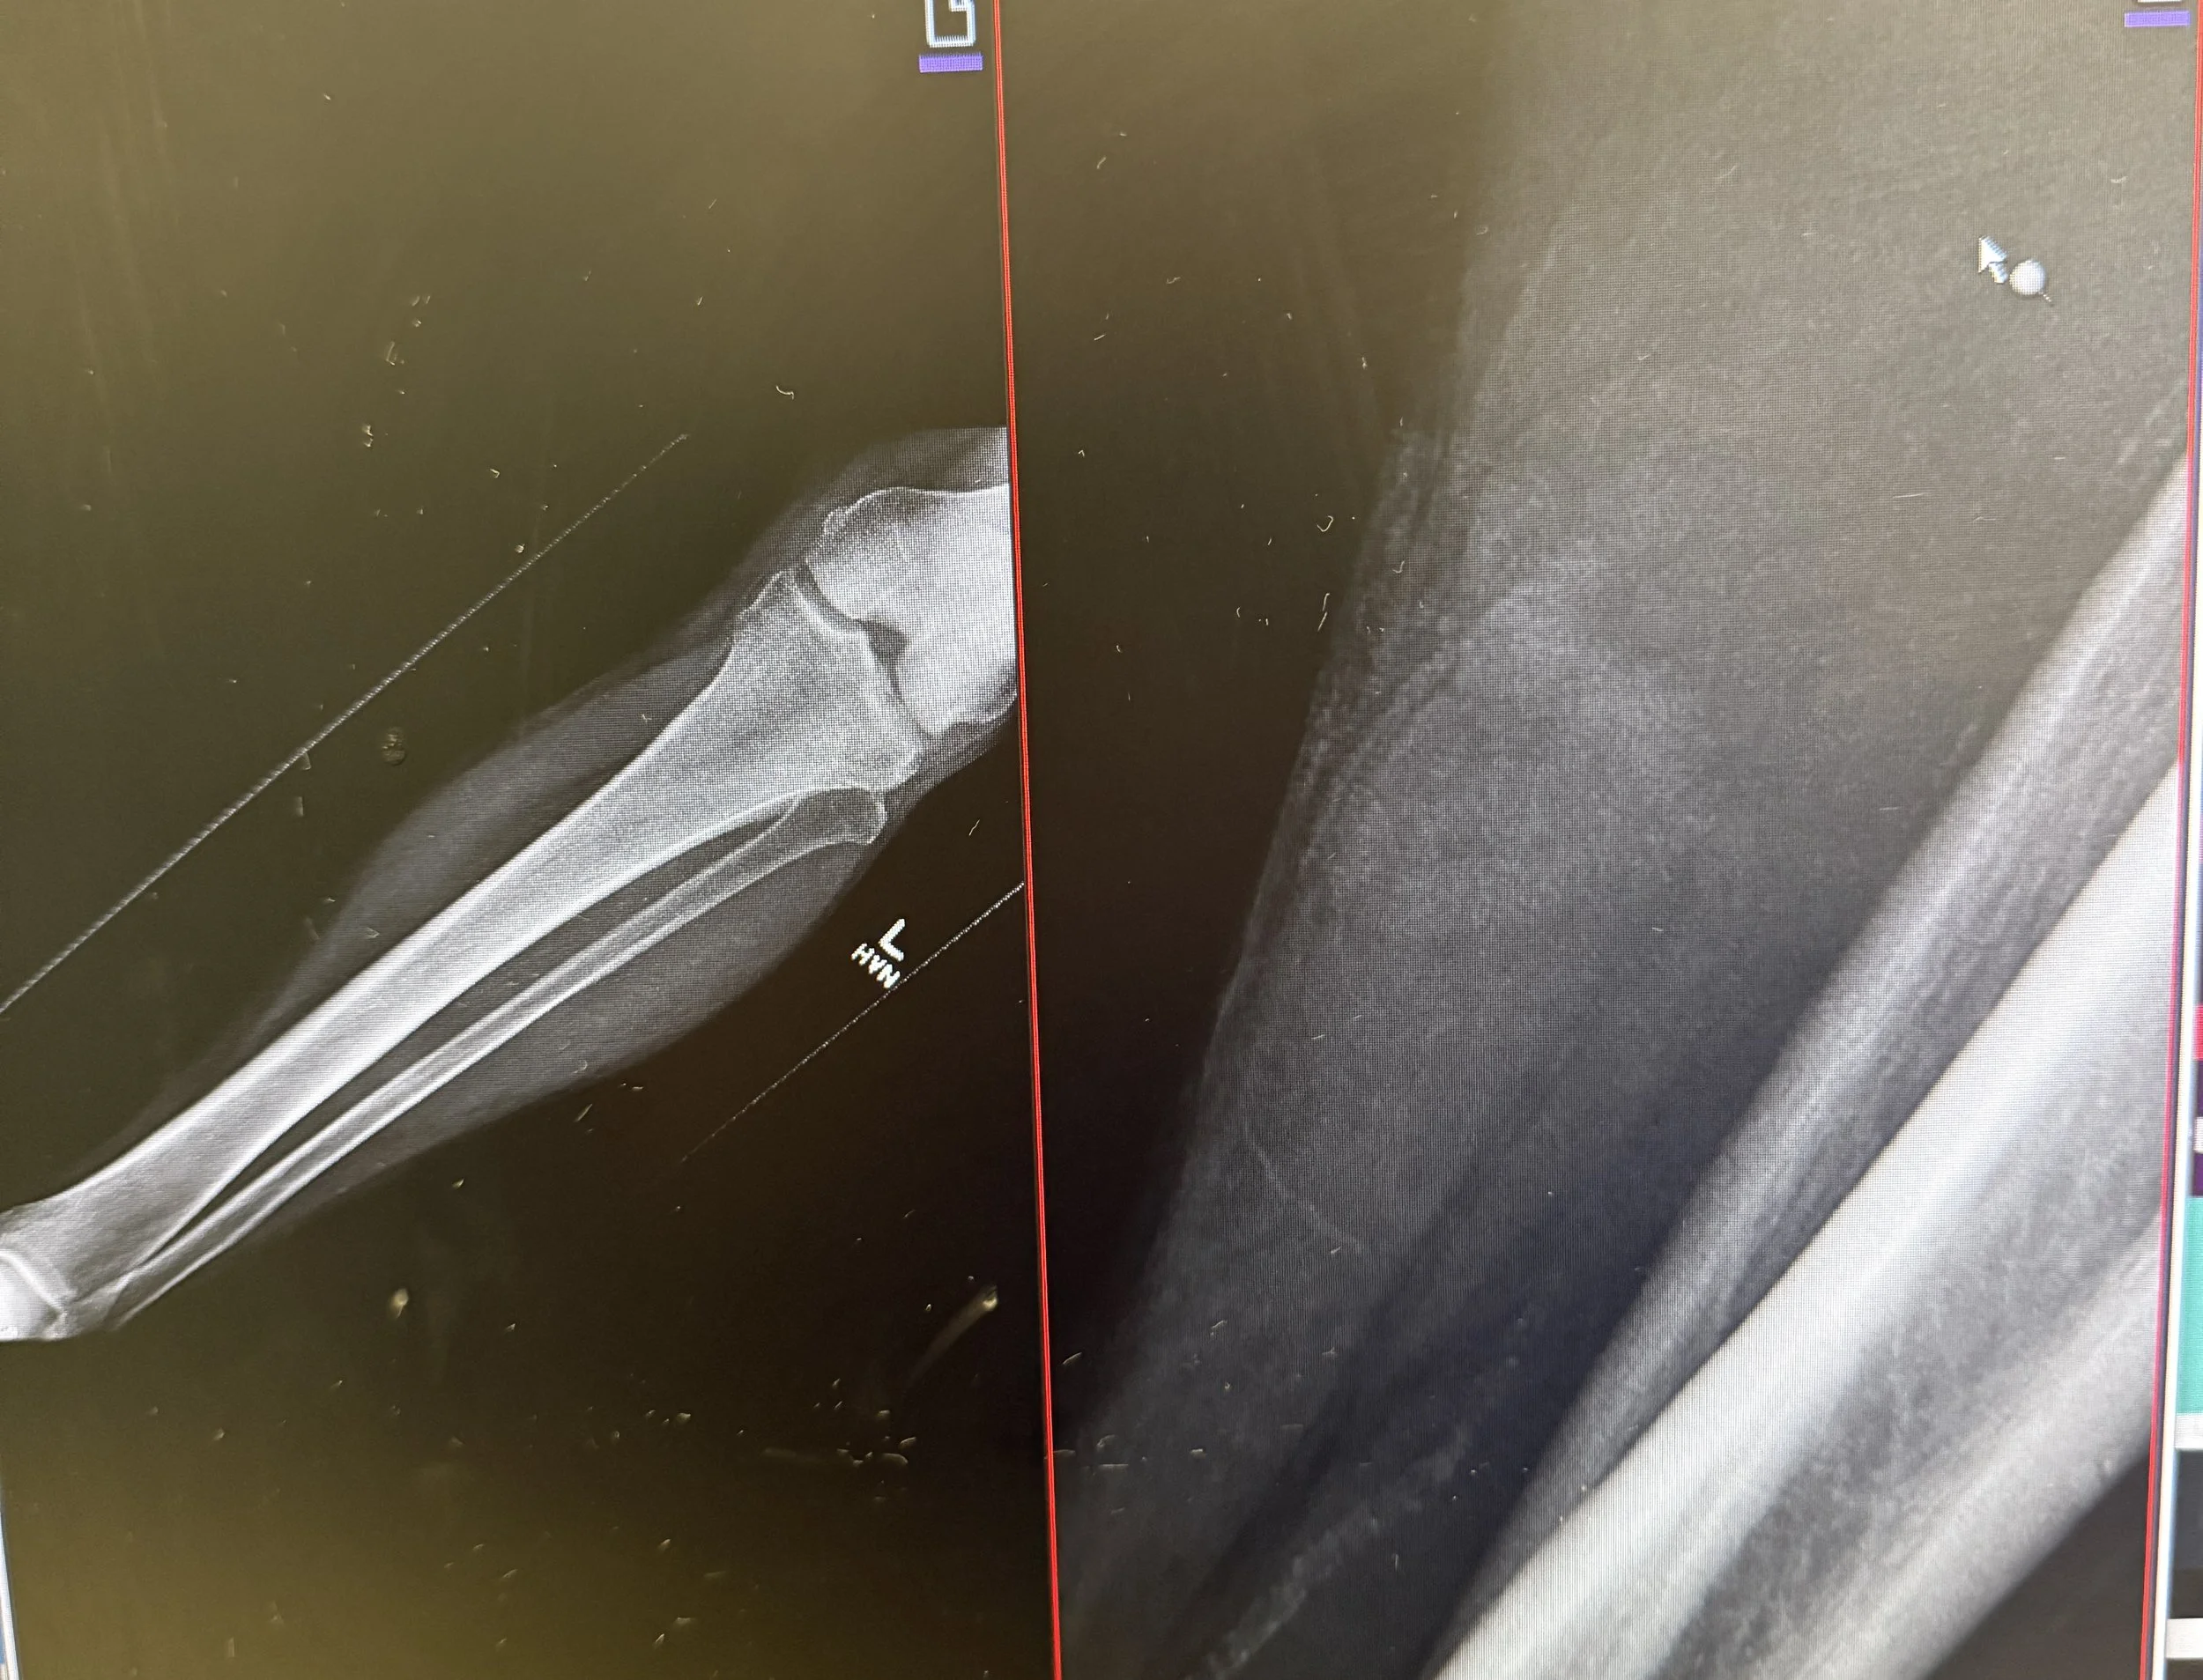

In the case shown here, a V-shaped flap laceration of the lower extremity was closed using a combination of vertical mattress sutures across the flap and simple interrupted sutures for the remaining wound.

Lower extremity lacerations present a unique set of challenges in the emergency department. The skin over the shin, calf, ankle, and foot is notoriously tight, with little redundancy. Vascular supply is less robust than in the face or scalp, and these wounds often exist in the context of trauma, contamination, or high shear forces. Primary closure using simple interrupted sutures may work for straightforward wounds, but when approximation creates excessive tension—or worse, when wound edges blanch—a different approach is needed.

Unlike the scalp or face, lower extremity wounds often resist approximation due to the combination of taut skin, minimal underlying soft tissue, and frequent contamination. Attempting to simply “pull the edges together” can create ischemia, wound edge necrosis, or dehiscence. Flaps provide: